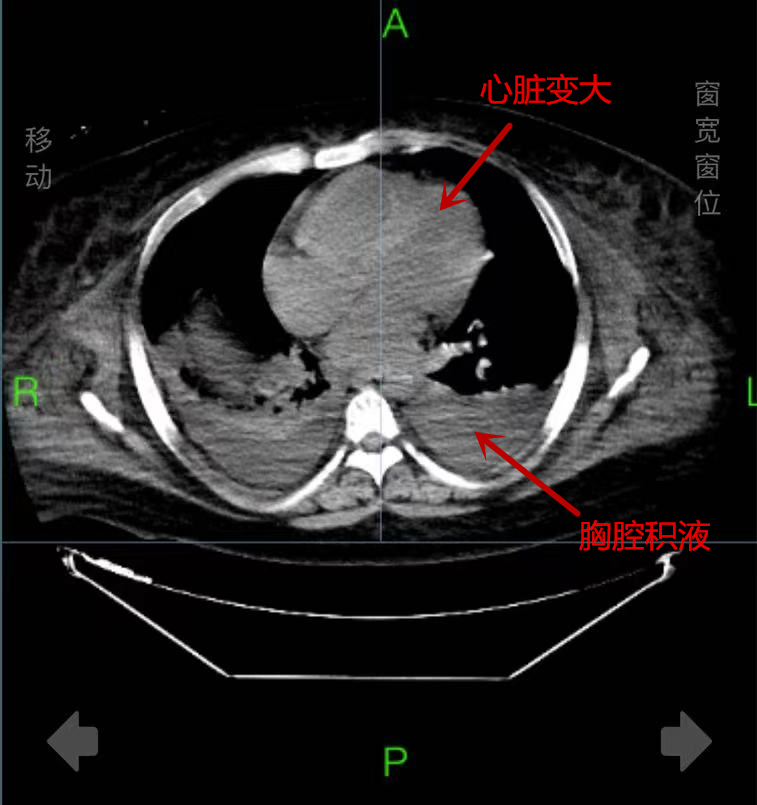

入院时,戴先生面色苍白,血氧饱和度低,全身高度水肿,情况十分危急。急诊三部主任张兴文、副主任医师徐静、贾爱军和护士长徐芙蓉等组成的医护团队立即组织抢救,给予患者利尿强心、补充白蛋白,无创呼吸机支持治疗等抢救措施。因患者体重太重,且高度浮肿,不仅输液抽血成问题,需要在超声引导下穿刺置管,连翻身检查都需要五六人齐上阵才能完成。经检查发现,患者心、肺功能衰竭,严重贫血、双侧胸腔积液、脂肪肝、皮下水肿,被诊断为重度营养不良、重度低蛋白血症、慢性营养不良性贫血和贫血性心脏病。住院期间,除了输血、利尿、强心和补充白蛋白等治疗外,医院营养体重管理专家蔡华教授还为戴先生制定了个性化的营养计划。通过10余天治疗,目前戴先生终于康复出院,且成功“瘦身”30斤。